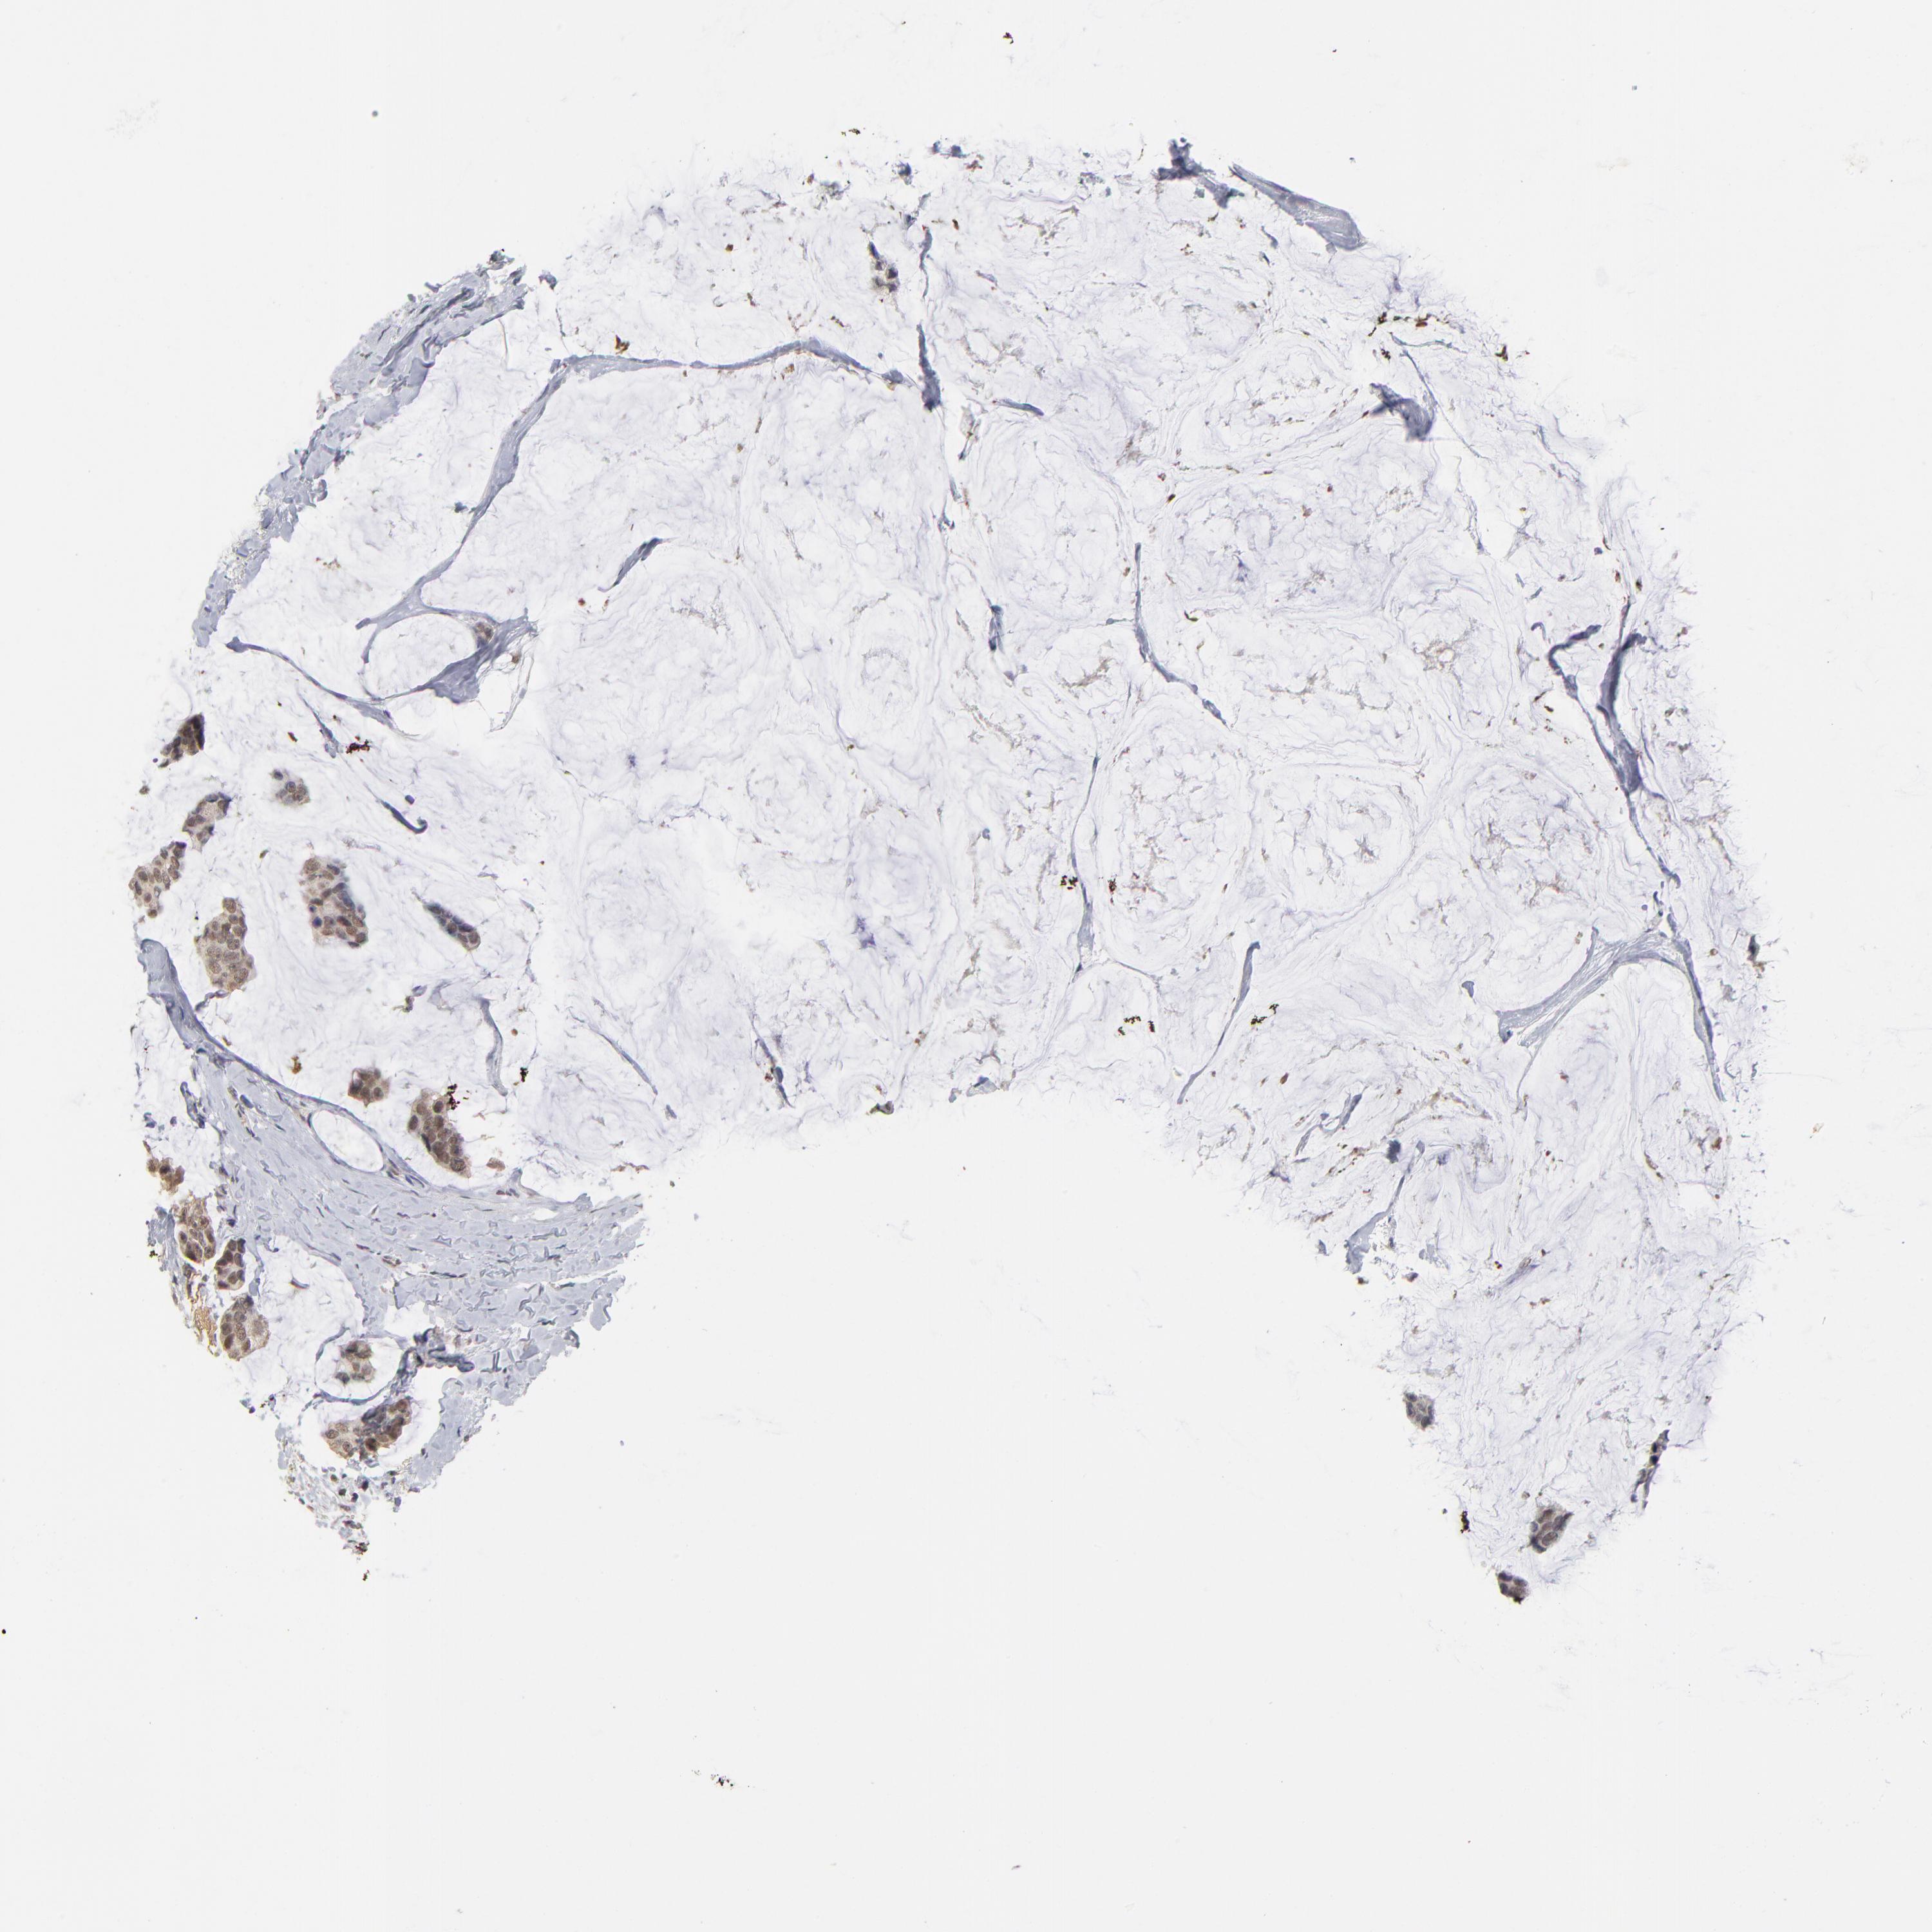

CANCER BREAST CANCER Show tissue menu

BRCA TCGA BRCA VALIDATION PROTEIN EXPRESSION